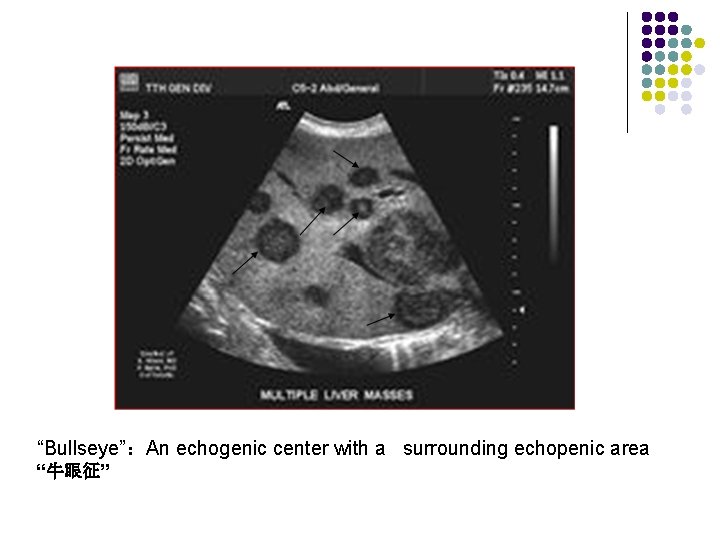

Metastases to liver l l l Organ of origin: colon(42%); stomach(23%); pancreas(21%); breast(14%); lung(13%) Number : multiple(98%); solitary(2%) “Bullseye”:An echogenic center with a surrounding echopenic area Echopenic : Less echogenic than the surrounding liver Echogenic More echogenic than the surrounding liver

“Bullseye”:An echogenic center with a surrounding echopenic area “牛眼征”

“Bullseye”:An echogenic center with a surrounding echopenic area

(bulls eye sign)